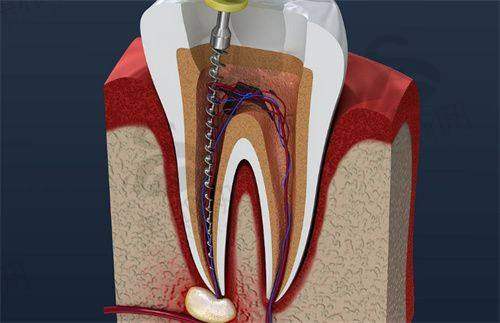

6. 牙体牙髓病治疗:开展根管治疗、补牙、嵌体修复等,采用显微镜根管治疗技术,精细定位根管,提高治疗成功几率,补牙材料选用进口树脂,美观且耐用。

6. 湖南省娄底市娄星区景辰口腔医院根管治疗(前牙):500 - 800元/颗

7. 湖南省娄底市娄星区景辰口腔医院根管治疗(后牙):800 - 1500元/颗